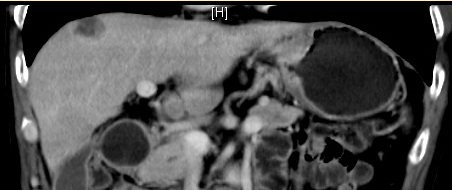

患者 李某某,男,65岁。2019-08外院胃镜提示:贲门巨大溃疡性病变。08-29我院病理会诊(H191689):贲门中分化腺癌。免疫组化:HER2(...